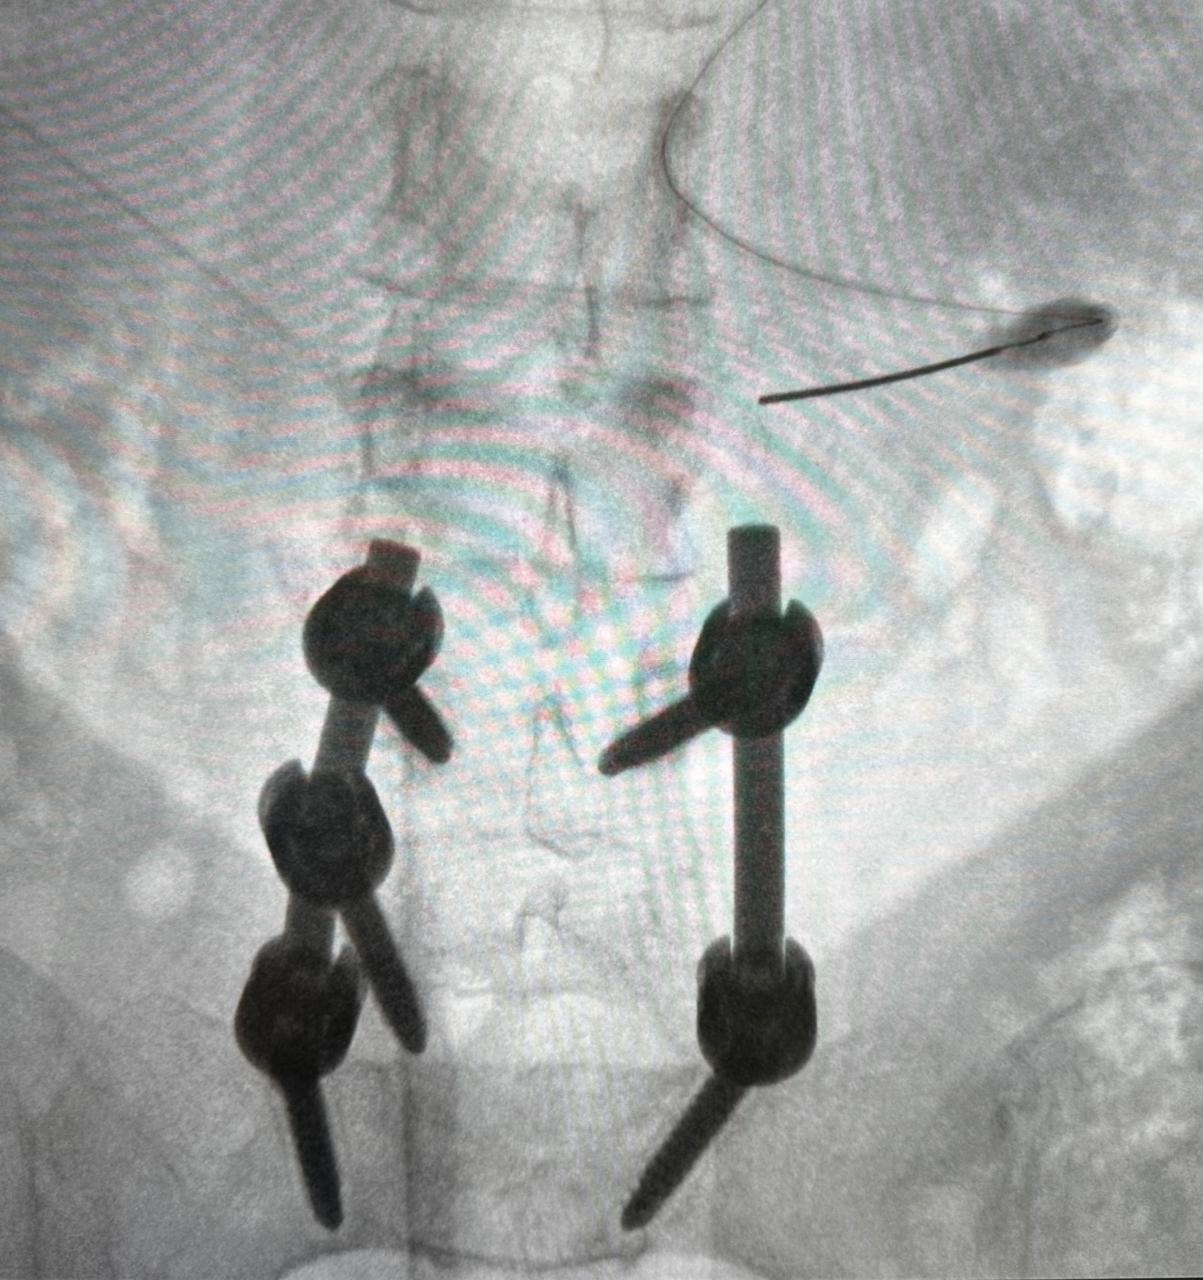

Radiofrecuencia de facetas lumbares